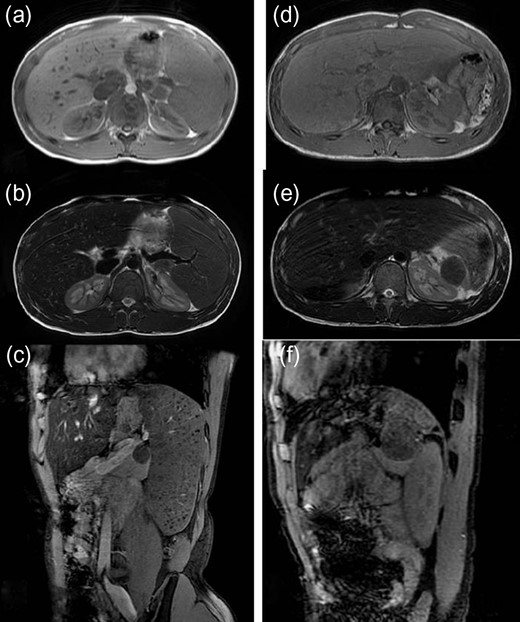

A 16-year-old boy was admitted with a rapidly growing pancreatic mass. He had received a diagnosis of HS based on the following: the need for a blood transfusion to treat anemia after birth, a history of hemolytic anemia, and a family history of HS. He had often undergone medical examinations for anemia and jaundice in junior and senior high school. When he was 15 years old, he visited our hospital because of the rapid onset of jaundice. Radiological examinations, such as computed tomography (CT) (Fig. 1a–c) and magnetic resonance imaging (MRI) (Fig. 2a–c), showed a huge spleen and a 2-cm mass near or in the pancreatic tail. Sonazoid-enhanced ultrasonography showed hypervascularity in the mass, which appeared to be located near the pancreatic tail and raised suspicions about an accessory spleen (Fig. 3a). The patient underwent a successful splenectomy by laparotomy, but the mass found on the preoperative examination could not be found by inspection and intraoperative ultrasonography (Fig. 4a and b). The mass grew rapidly to 4 cm one year after splenectomy, as shown on the radiological examinations (Figs 1d–f, 2d–f and 3b), but a recurrence of HS with anemia or jaundice did not develop. However, he underwent successful laparoscopic surgery to aid in the differential diagnosis. After the adhesions of the omentum to the abdominal wall were detached, the laparoscopic ultrasonogram revealed the mass in the pancreatic tail. He underwent laparoscopic distal pancreatectomy (Fig. 4c and d), and he had no clinical symptoms or signs of local infection or sepsis. A CT on the ninth postoperative day showed a small peripancreatic collection (Grade B: the clinical grading of postoperative pancreatic fistula). He was discharged on the 11th postoperative day. The resected specimen revealed the intrapancreatic mass that was covered with pancreatic tissues, and the intrapancreatic mass was an accessory spleen (Fig. 4e).

Magnetic resonance imaging (MRI) (before and after splenectomy). (a–c) Before splenectomy: MRI shows a huge spleen and a 2-cm mass in the pancreatic tail. (d–f) After splenectomy: MRI shows the mass in the pancreatic tail grows rapidly to 4 cm.